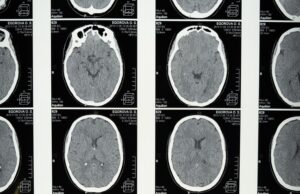

Avicenna.AI announced today that it has received 510(k) clearance from the US Food and Drug Administration (FDA) for its CINA-ASPECTS and CINA-iPE products.

CINA-ASPECTS is...

Avicenna.AI receives CE mark for AI tool to assess stroke severity

Medical imaging AI specialist Avicenna.AI has received CE mark certification for its CINA ASPECTS AI tool for stroke severity assessment. CINA ASPECTS automatically processes...

Avicenna.AI secures FDA clearance for its CINA Head neurovascular imaging artificial...

Medical imaging artificial intelligence (AI) specialist Avicenna.AI has announced it has received 510(k) clearance from the US Food and Drug Administration (FDA) for its...